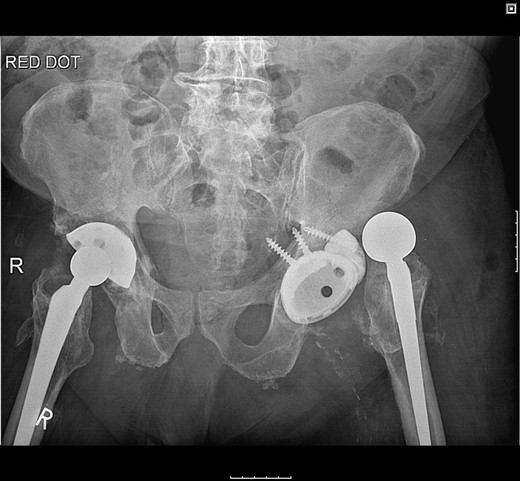

The femoral stem was kept firm in its proper position. Structural porous titanium acetabular augment (Regenerex™), reinforced with a cancellous allogeneic bone graft, was used to reconstruct the superior acetabular wall. The cup was completely revised using a Biomet® Regenerex Ringloc® multihole 56-mm acetabular cup and a Hi-wall Ringloc-x PE 54-mm liner. The previous 32-mm femoral head was replaced with a Bioball® 36-mm metal head and a Bioball® adapter standard (0 mm) Taper 11/13 (4° 3°), correcting the offset and achieving stability (Fig. 4).

A post-revision radiograph demonstrating a structural graft using the acetabular augment (Regenerex™) and revised cup in situ.